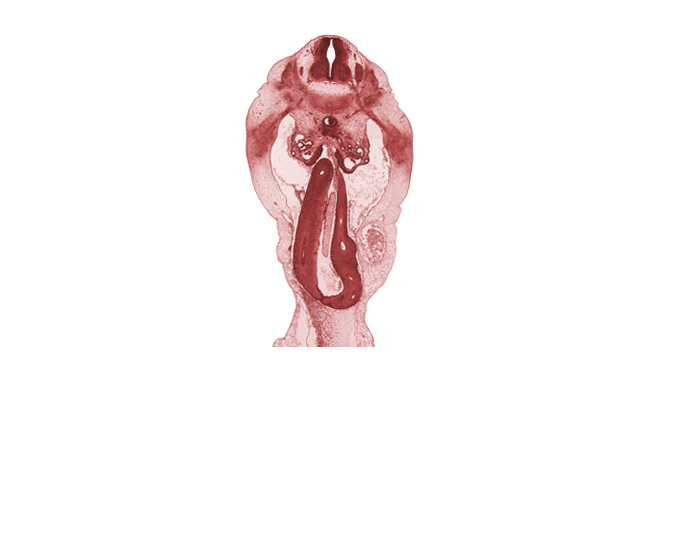

0 μm

Carnegie Embryo #6520 | Location: 23-04-05

Keywords: L-1 spinal ganglion, L-1 spinal nerve, aorta, caudal edge of superior mesenteric artery, cecum, distal limb of herniated midgut, duodenum, mesenchyme in mesentery of herniated midgut, mesonephric vesicle(s), proximal limb of herniated midgut, umbilical coelom, umbilical vein

Source: The Virtual Human Embryo.